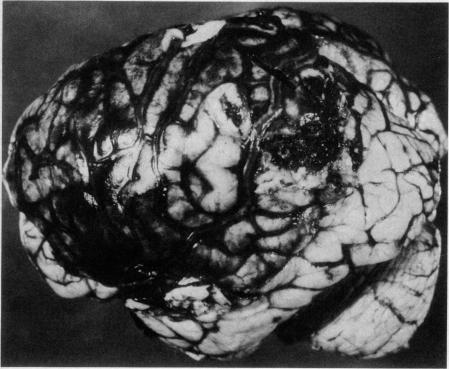

Four days after the onset of a severe headache a 22-year-old woman who had been taking oral contraceptives for less than three weeks had a convulsion, followed by right hemiparesis. Other focal neurologic signs and evidence of raised intracranial pressure appeared, and she became comatose on the seventh day. A left craniotomy revealed extensive cerebral venous thrombosis. She died the next day. On postmortem examination extensive thrombosis of the superior sagittal sinus and draining cerebral veins, and multiple areas of cerebral hemorrhage and hemorrhagic infarction were seen. Some of the superficial cerebral veins showed focal necrosis of their walls, and the lateral lacunae of the superior sagittal sinus contained proliferating endothelial cells. The adrenal veins were also thrombosed. The significance of these findings is discussed. The literature on cerebrovascular complications of oral contraception, particularly cerebral venous thrombosis, is reviewed.

一名22岁女性,服用口服避孕药不到三周,在严重头痛发作四天后出现惊厥,随后出现右侧偏瘫。其他局灶性神经体征及颅内压升高的证据出现,她在第七天昏迷。左侧开颅手术显示广泛的脑静脉血栓形成。她于次日死亡。尸检发现上矢状窦及引流脑静脉广泛血栓形成,并有多处脑出血和出血性梗死。一些脑浅表静脉显示管壁局灶性坏死,上矢状窦外侧陷窝内可见内皮细胞增生。肾上腺静脉也有血栓形成。讨论了这些发现的意义。综述了口服避孕药脑血管并发症的文献,特别是脑静脉血栓形成方面的文献。